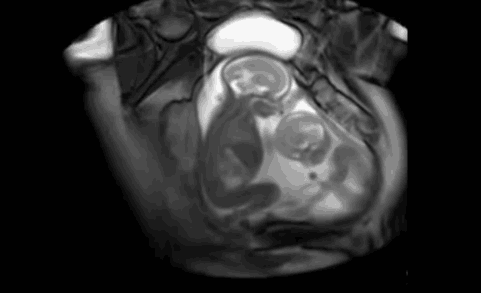

今天,张杰在微博宣布,谢娜诞下一对双胞胎女儿。太阳女神真的辛苦了。